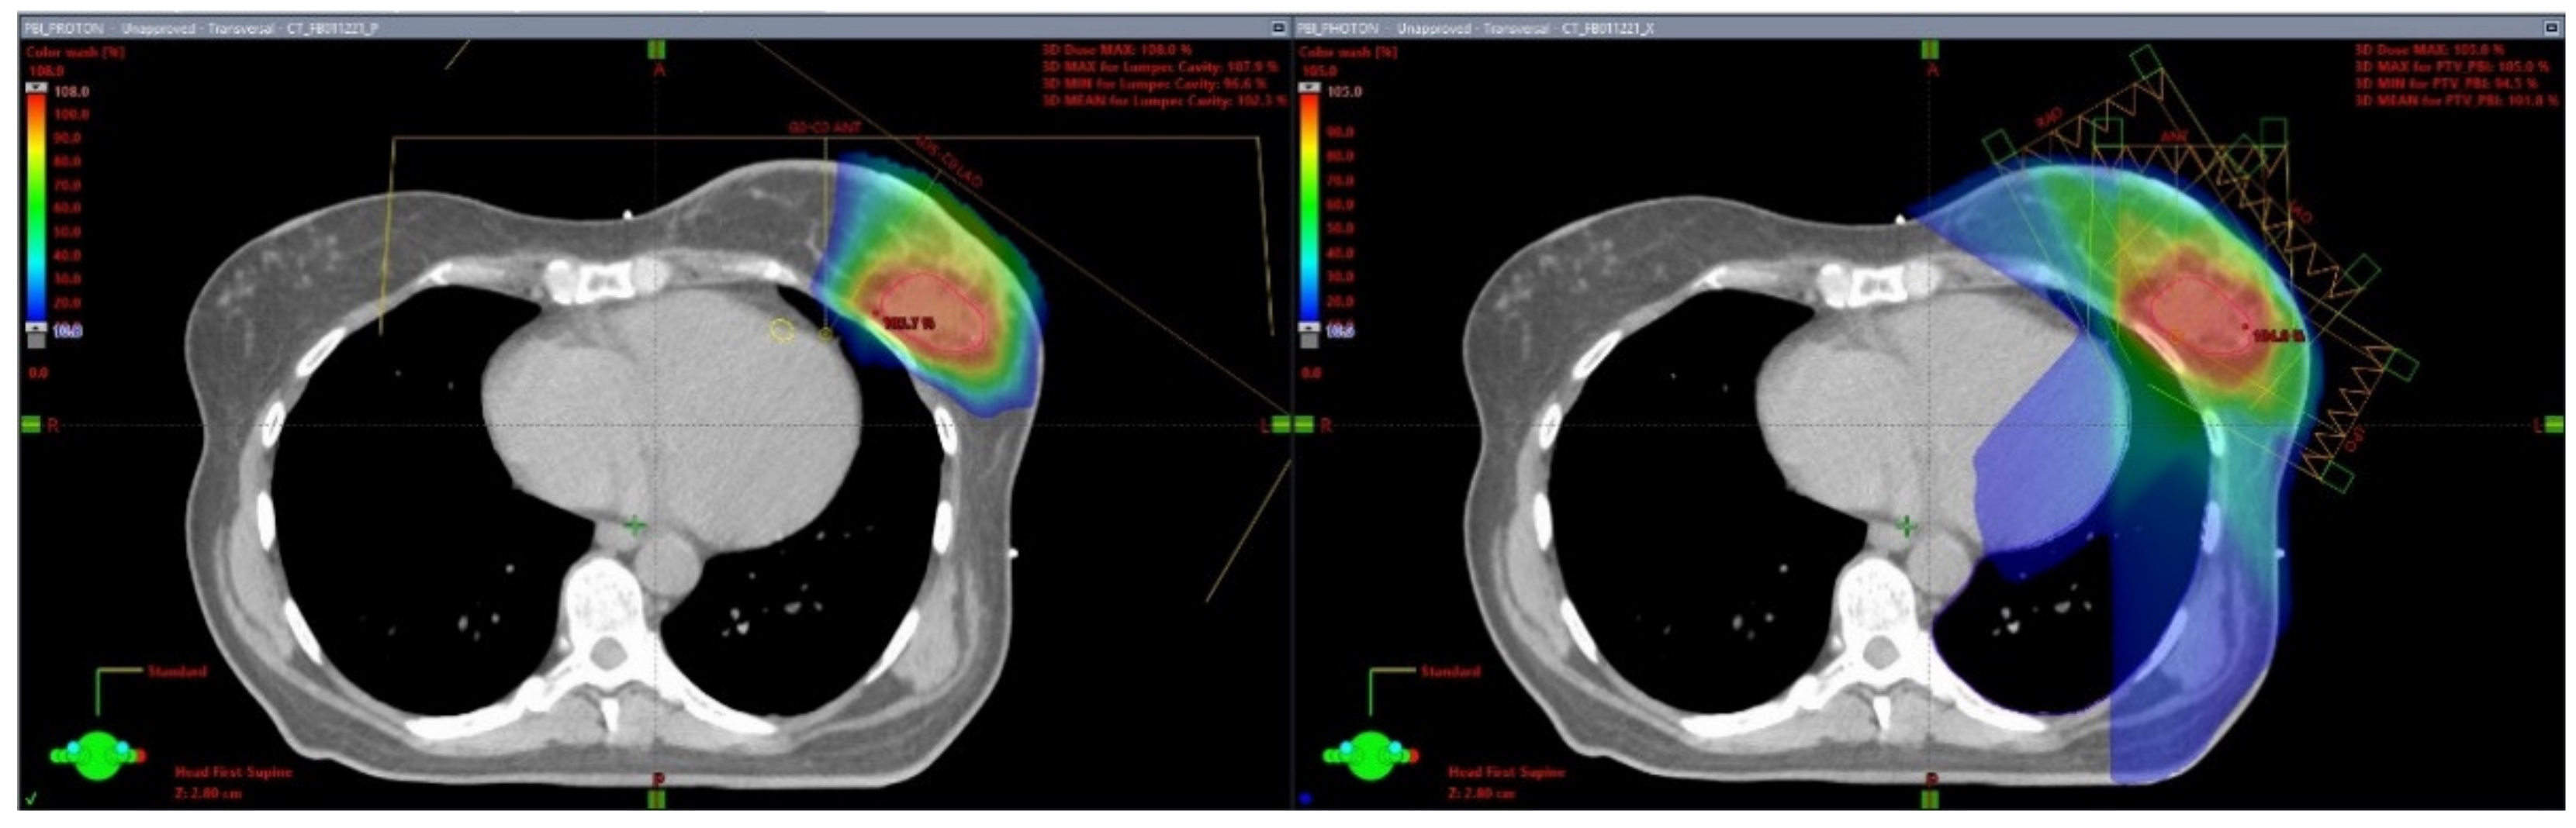

Several institutional series have reported on the use of PT for PBI. Dosimetric studies have demonstrated the superiority of PT in sparing lungs, heart, and nontarget breast tissue compared with other external beam PBI modalities [20,21,22,23,24]. (Figure 1) PT also results in a far more homogeneous treatment plan compared with brachytherapy techniques, resulting in reduced maximum doses to the ipsilateral breast tissues, potentially reducing the risks of breast tissue fibrosis and fat necrosis [25].

Figure 1.

Proton and Photon Partial Breast Irradiation Treatment Plans. This is a patient with a left-sided breast cancer receiving partial breast irradiation. The left image is a representative axial slice of a proton plan using two treatment fields (anterior and left anterior oblique). The right image is a representative axial slice of a photon static-field intensity-modulated radiation therapy (IMRT) plan using 4 fields (right anterior oblique, anterior, left anterior oblique, and left posterior oblique).